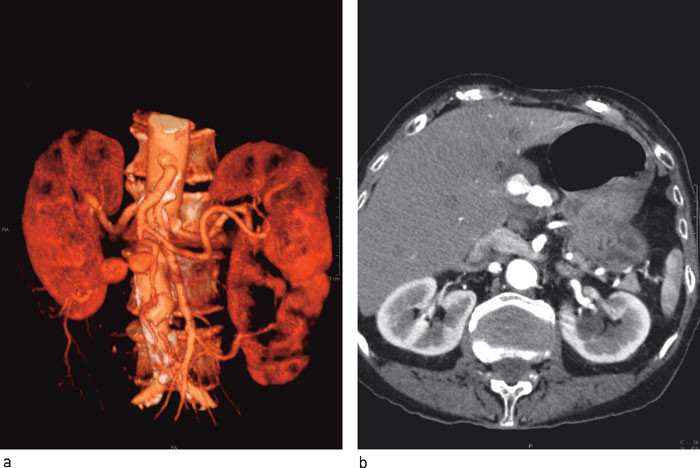

Pasienten ble overflyttet til Rikshospitalet for invasiv koronarutredning. Det ble ikke påvist signifikant koronarsykdom. Funksjonen i venstre ventrikkel ble ansett som god, og hun ble flyttet tilbake til vår avdeling. Her ble det utført CT-undersøkelse som bekreftet mistanken om et aneurisme i forløpet av a. hepatica. Aneurismet ble beskrevet som tobuklet og det var lokalisert ekstrahepatisk svarende til a. hepatica propria, rett etter avgangen av arteria gastroduodenalis. Største diameter ble målt til 3,2 cm. Man fant ikke kontrastfylning perifert for aneurismet (fig 1).

Digital subtraksjonsangiografi viste åpne forhold til og med den proksimale buklen av aneurismet, med åpen a. gastroduodenalis. Det var tilkommet trombosering av den distale buklen av aneurismet (fig 2). Klinisk var pasientens tilstand uforandret, med symptomer som vi tilskrev aneurismet. Det ble ikke registrert stigning i leverfunksjonsprøver.